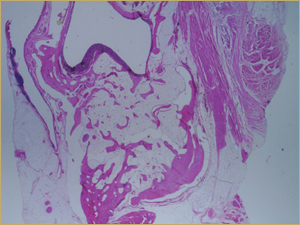

Figure 3a: Low-power histologic examination of rabbit maxillary sinus augmented with autogenous bone graft at 2 weeks after grafting. Hematoxylin and eosin (H&E) stain, 50× magnification.

After 2 weeks, grafted mature cortical bone fragments were present in the rabbit maxillary sinuses augmented with autogenous bone grafts (Fig. 3a). Few lacunae within the grafted bone were occupied by osteocytes (Fig. 3b). The margins of the grafted particles demonstrated active bone turnover and remodelling. Resorption of the grafted mature cortical bone was coupled with areas of newly formed woven bone. The new bony regenerate demonstrated plump osteocytes and osteoblasts.